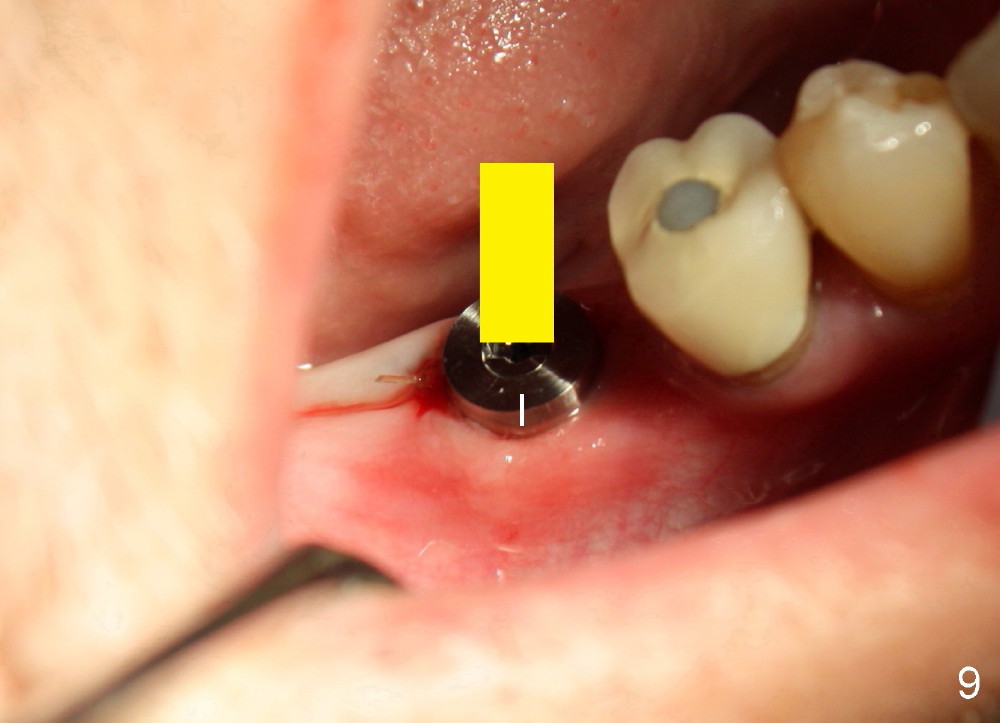

When the pilot drill is inserted into the initial osteotomy site for X-ray confirmation of its depth (Fig.7: D), the vertical block of the endo device (yellow rectangle) may be blocked due to the narrow divided edentulous space. The crown of the molar is shown, whereas the inferior alveolar nerve is not shown except a small portion in the left lower corner of Fig.7 (pink line). The depth of the further osteotomy (Fig.8: O) was chosen without accurate estimate. The integrity of the inferior alveolar canal (IAC) was violated, although the implant (I) was not placed that deep. The patient experienced transient postop pain, which was controlled by Medrol Dosepak. A correct way to prevent iatrogenic neuropathy in this situation is to remove the pilot drill, and place the endo device as deep as possible. The new X-ray should be able to reveal the relationship of the end of the osteotomy (shadow) to IAC. Measurement must be done using digital X-ray software over the new image to determine how deep osteotomy should be made (as shown in Fig.10). When an implant is placed (I in Fig.9: a second case as will be shown in Fig.10-12), the vertical block of the endo device can be placed on the implant. The sensor is placed deep into the lingual vestibule to show IAC in relation to the implant (Fig.8).